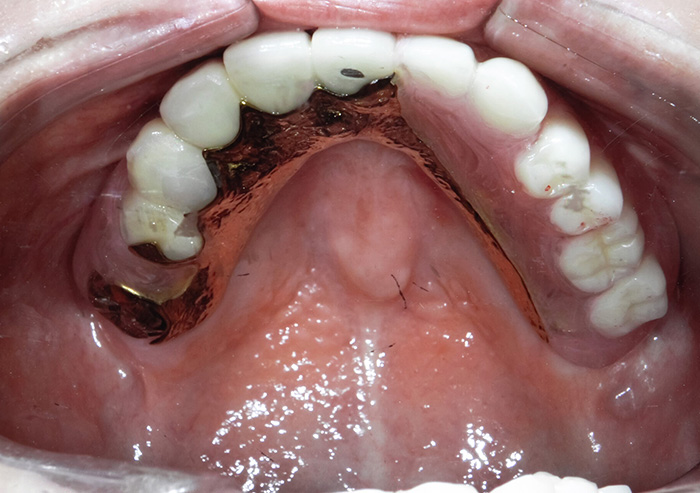

奥歯(大臼歯)の銀歯が気になる方は、ご相談ください。